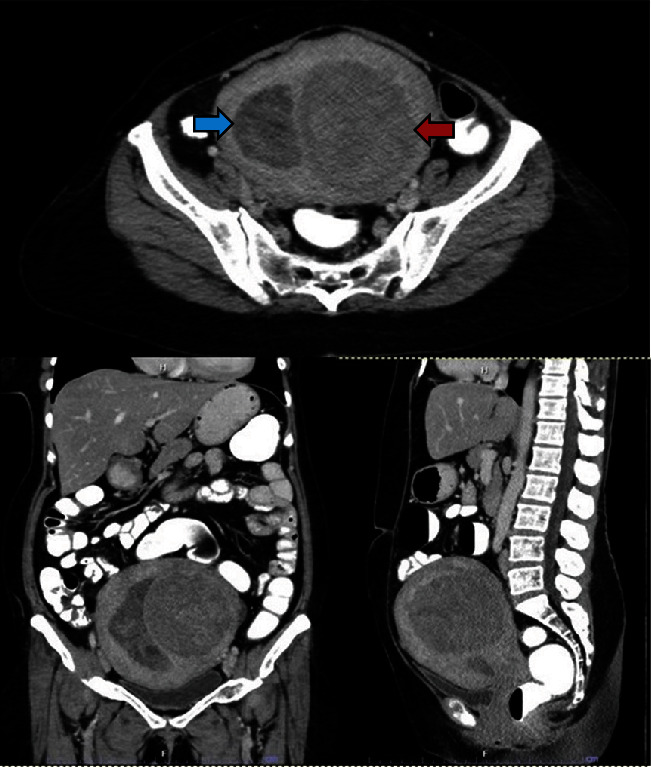

子宫内膜息肉是子宫内膜腺体和基质在子宫腔内无序生长的良性肿瘤。它们与不孕症、异常子宫出血和使用他莫昔芬有关。虽然大多数息肉的大小小于 2 厘米,但罕见的巨大息肉会引起恶性肿瘤的担忧。我们报告了一例 58 岁女性的 15 厘米巨大子宫内膜息肉病例,该女性有服用他莫昔芬的病史,并以便秘为常见主诉。此外,我们还对巨型子宫内膜息肉病例进行了文献综述。该病例是迄今为止报告的最大的子宫内膜息肉。

Endometrial polyps are benign disorganized growth of endometrial glands and stroma in the uterine cavity. They are associated with subfertility, abnormal uterine bleeding, and tamoxifen use. While most polyps are smaller than 2 cm in size, rare giant polyps can cause concerns over malignancy. We report a case of a 15 cm giant endometrial polyp in a 58-year-old woman with a history of tamoxifen use who presented with an uncommon complaint of constipation. Additionally, a literature review of giant endometrial polyp cases is presented. This case represents the largest reported endometrial polyp to date.